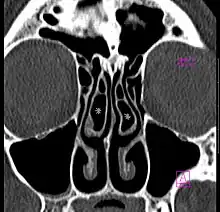

Large concha bullosa -